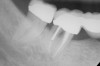

Figure 5  Recurrent decay of teeth Nos. 11 and 12. Note the proximity of the decay on both teeth to the osseous crest.

Figure 5

In treatment planning, the decay rate of the patient’s teeth, including the endodontic status of the individual tooth, becomes an important factor when considering long-term outcomes. In the pictured case (Figure 5), tooth No. 11, which previously had been treated endodontically, had recurrent decay and tooth No. 12 had advanced decay with endodontic involvement. In less than 30 days, recurrent decay that reaches the endodontic fill through a leaky restoration (temporary or not), ill-fitting crowns, or broken fillings can re-infect the entire length of the root canal system in a previously endodontically treated tooth.22 Therefore, saving a previously endodontically treated tooth, as in this case, may involve endodontic re-treatment, which can be a deciding factor for tooth preservation.

In addition, xerostomia becomes more likely with advanced patient age and/or the use of certain medications.23 This problem can lead to a higher decay rate, which has implications for a situation similar to the above case. In this case, in which tooth No. 12 would need endodontic treatment, surgical crown lengthening, a post, a crown, etc, to save it, the alternative of extraction and implant placement should be considered. The implant would not be susceptible to future decay, root fracture, or endodontic failure. The fee for this treatment also may be comparable to tooth preservation. If the tooth also requires a post, core, or other treatment, then its prognosis24 would be less optimistic than that of a dental implant. Also, if the implant can be placed at the time of extraction, there would be only one surgical visit; whereas, the endodontic and crown-lengthening procedures usually involve many treatment visits.

Bone removal is also a factor. In this example, tooth No. 12 had a short root. Removal of bone to reestablish a 3-mm biologic width as well as about 2 mm of ferrule25 would decrease the long-term prognosis of the tooth, especially because there would be an existing compromise regarding the crown-to-root ratio.26 Osseous recontouring for crown lengthening also may remove bone from the adjacent teeth (in this example, the distal of tooth No. 11).